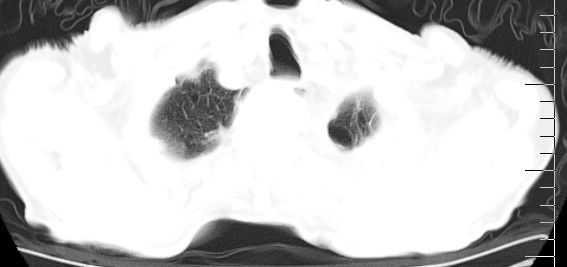

标题: CT10141:男、84岁,咳嗽、咯血1年。 [打印本页]

标题: CT10141:男、84岁,咳嗽、咯血1年。

支持左侧中央型肺癌伴下叶肺不张\\纵隔淋巴结转移.左侧包裹性胸腔积液\\心包积液.左侧少量胸腔积液..慢性支气管炎伴部分间质纤维化.

支持:左侧中央型肺癌伴下叶肺不张\\纵隔淋巴结转移.左侧包裹性胸腔积液\\心包积液.左侧少量胸腔积液..慢性支气管炎伴部分间质纤维化.另:支气管分支根部明显阻塞 狭窄,内膜凸凹不平,提示内膜增生物。

咯血病史较长,左肺下叶实变,体积未明显缩小,隐约可见血管影及坏死阴影,双肺门及纵隔淋巴结增大,心包增厚积液,纵隔右移位,单侧胸腔积液,首先考虑:大叶型肺泡癌伴纵隔心包转移。

左下中央型肺癌伴阻塞性不张,肺炎,左侧包裹性胸腔积液\\心包积液

左肺中心性肺癌并左肺下叶肺不张,纵隔淋巴转移、同侧胸腔及心包积液(转移)。

左肺中心性肺癌并肺不张,同侧 胸膜及心包转移,左肺癌性淋巴管炎